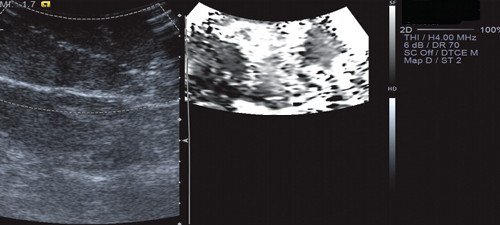

Рис. 12. Эластография с ручной компрессией (в режиме серошкального кодирования). Объемное образование печени - мягкой консистенции и не отличалось от неизмененной паренхимы печени. Коэффициент компрессии QF = 70.

Рис. 13. Эластография с ручной компрессией (в режиме цветового кодирования). На эластограмме видно, что объемное образование печени - мягкое с жесткими включениями (вариант эластограммы № 3).